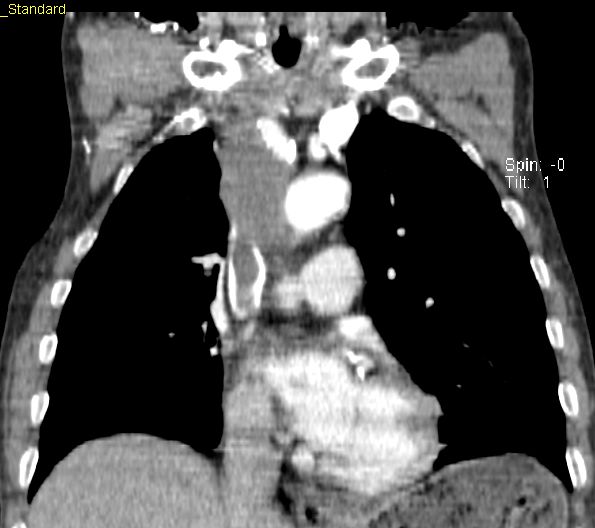

CT Infiltration des oberen Mediastinums. Flottierender Thrombus in der Vena cava superior.